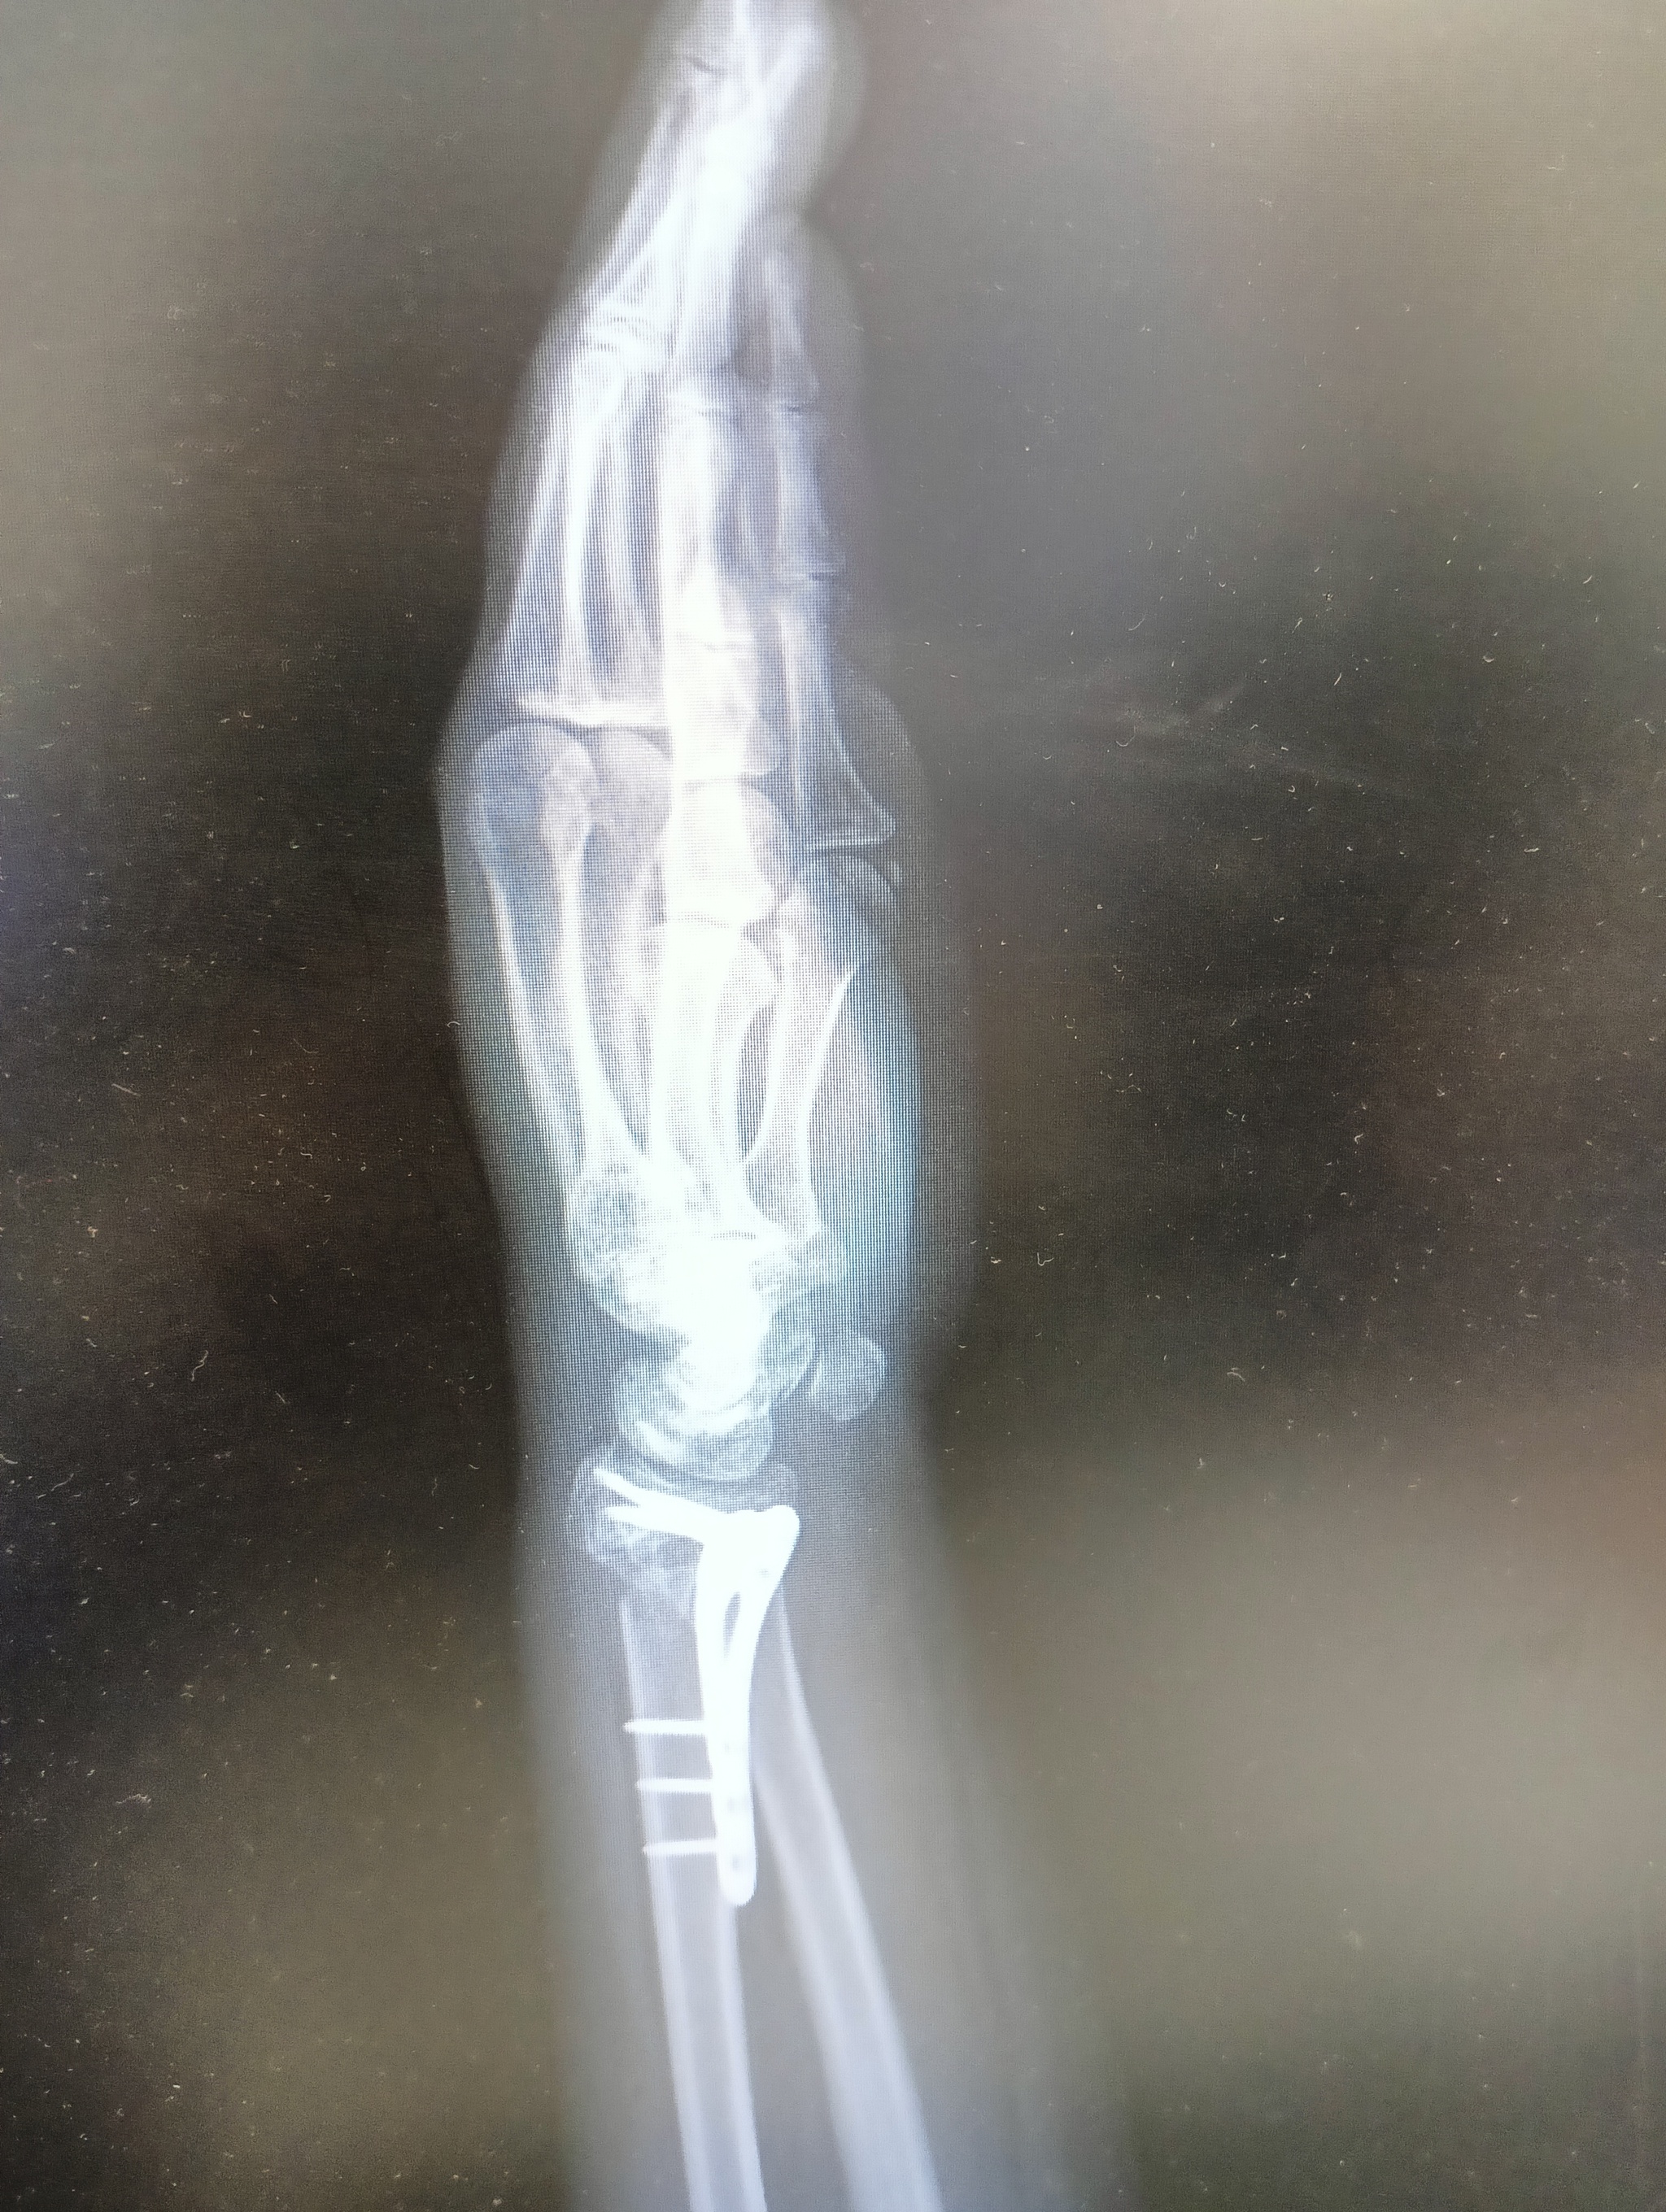

22 июля я неудачно упала и получила оскольчатый перелом дистального метафиза лучевой кости со смещением отломков более чем на 1/2 ширины диафиза. Открытый перелом шиловидного отростка локтевой кости. Была месяц в гипсе, но ничего не срослось. Диастаз костных отломков стал до 4 мм. Локтевая ушла в сторону на 5 мм. На 3 месяц после перелома мне сделали операцию, поставив титановую пластину. Сегодня сделала ренген и получила вот такой результат: Застарелый сомнительно консолидирующийся перелом дистального метафиза правой лучевой кости в условиях накостного МОС. Помимо отрыва шилообразного отростка локтевой кости, видно, имеется разрыв дистального радио-ульнарного сочленения.

верхние ффото через 2 месяца после перелома, потом после операции и 2 нижние - сегодня